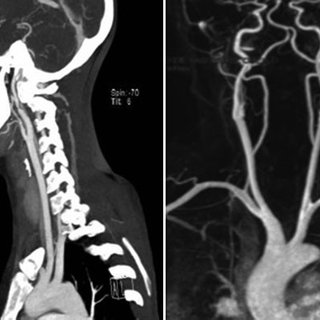

Cirugía Cerebrovascular

Neurocirugía cerebrovascular avanzada, enfocada en precisión microquirúrgica y resultados neurológicos óptimos.